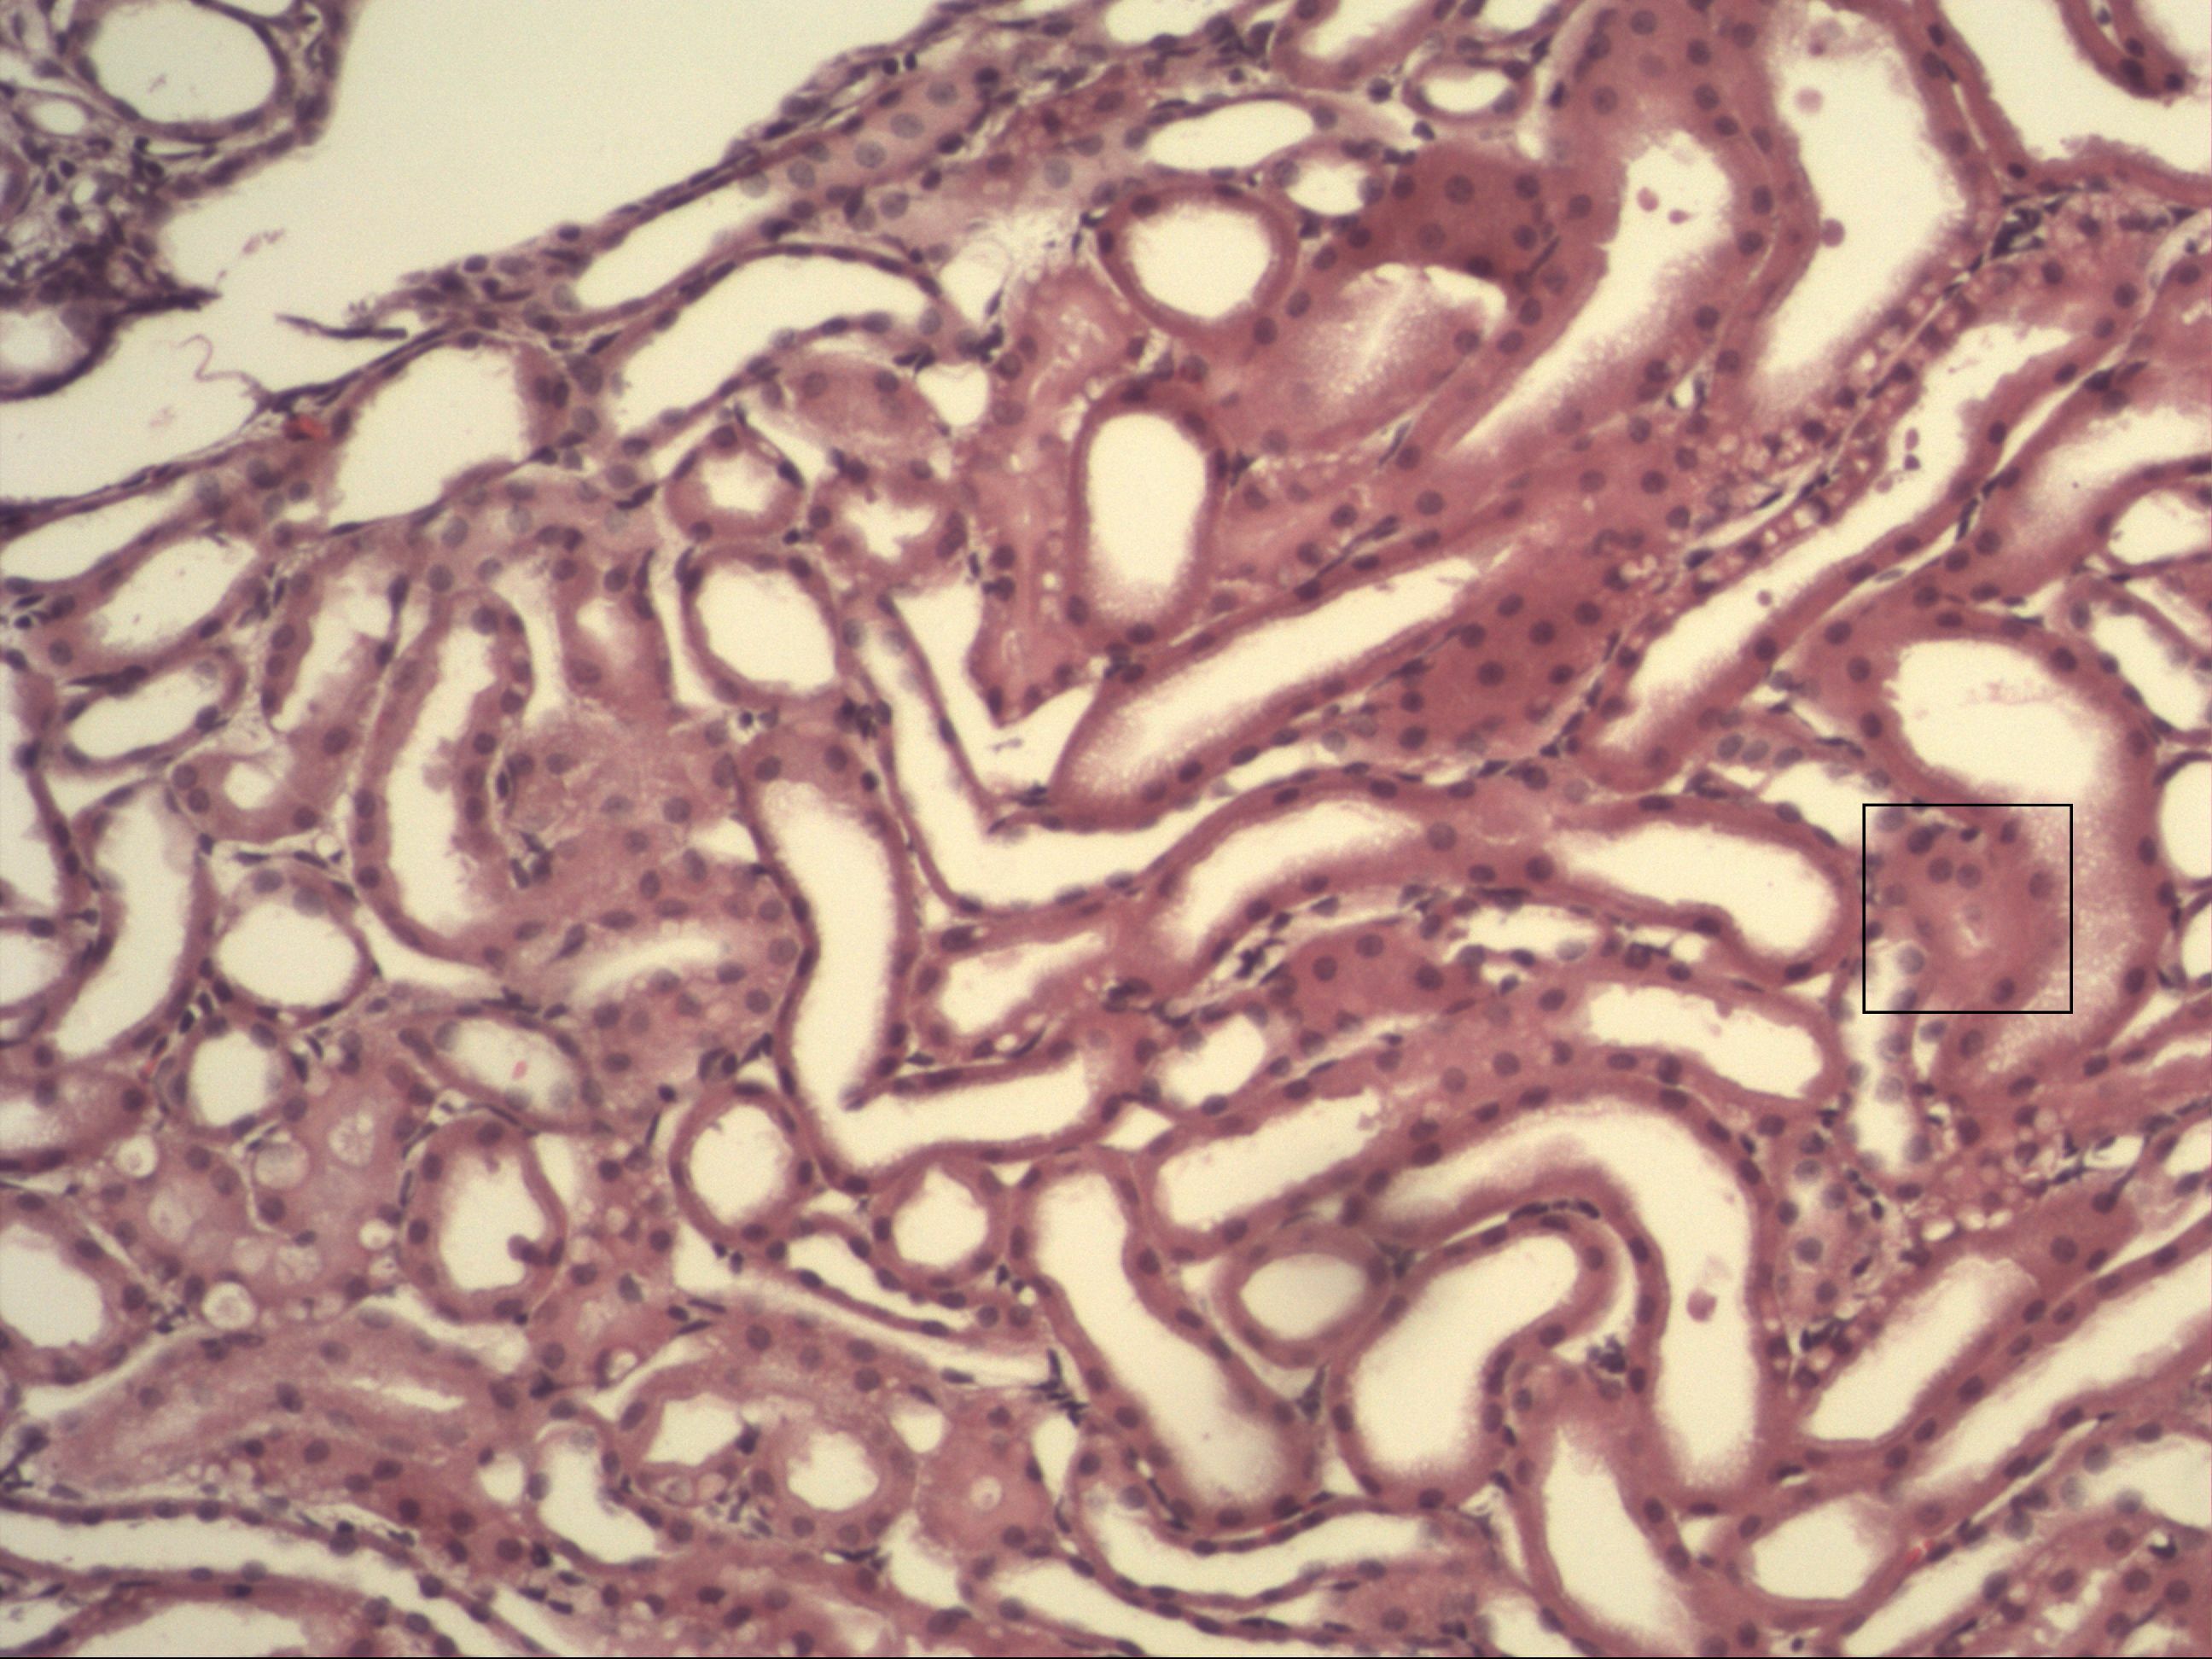

Niere [HE]

Ein histologischer Schnitt des Nierengewebes. Man erkennt Tubuli. Sammelrohre sind nicht zu erkennen. Diese sind größer und die Zellgrenzen lassen sich besser unterscheiden.